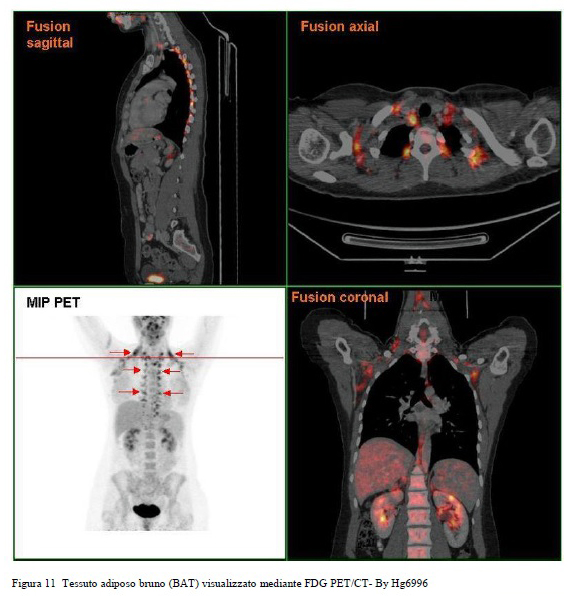

Il tessuto adiposo bruno (BAT) è particolarmente abbondante, oltre che negli animali che vanno in letargo, nei neonati dell’uomo e diminuisce con l’avanzare dell’età. Il BAT nell'uomo è localizzato principalmente in sede paracervicale, sopraclavicolare, interscapolare, perirenale (Figg. 11, 12).

In tali sedi i depositi del BAT hanno rapporti rilevanti con i vasi sanguigni che possono, così veicolare, tramite il flusso sanguigno il calore prodotto (Cold Induced Non Shivering Thermogenesis o NST) al resto dell’organismo.

Figura 11 Tessuto adiposo bruno (BAT) visualizzato mediante FDG PET/CT- By Hg6996